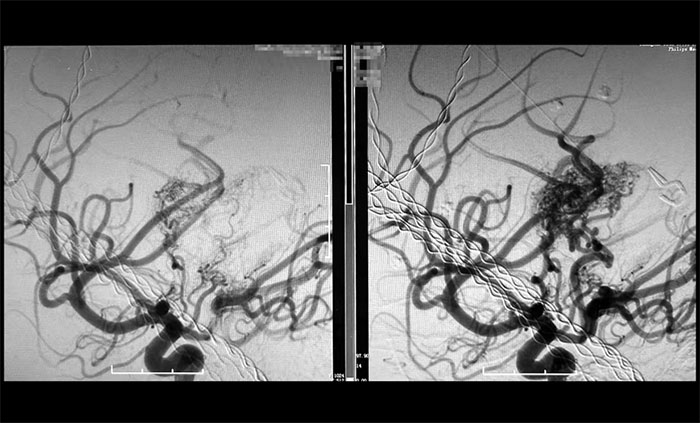

经过数小时的精雕细琢,手术团队成功栓塞预期目标责任血管。术后造影显示,假性动脉瘤已完全消失,畸形血管团达到预期栓塞效果,所有正常血管血流保持通畅(mTICI 3级)。

巨大脑动静脉畸形(右),被顺利栓塞(左)